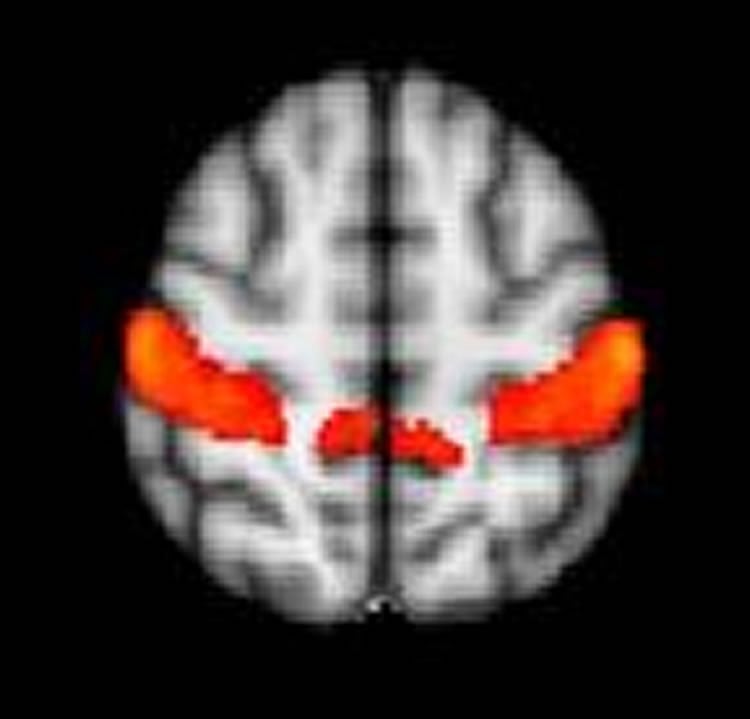

The team found that study participants with ASD and SOR had stronger brain responses to the sensory stimuli in brain areas that process sensory information, the primary somatosensory and auditory cortices, as well as in the amygdala, one of the brain’s emotional centers. The brain responses were even more severe when participants with ASD and SOR were exposed simultaneously to the auditory and tactile stimuli. They also found that all study participants showed a similar initial brain response to the stimuli, but youth with ASD and SOR were much slower in getting used to the stimuli — and reducing their brain response — than were children with ASD but not SOR.

Results: The mean age in both groups was 14 years and the majority in both groups (16 of 19 each) were male. Compared with neurotypical control participants, participants with ASDs displayed stronger activation in primary sensory cortices and the amygdala (P < .05, corrected). This activity was positively correlated with SOR symptoms after controlling for anxiety. The ASDs with SOR subgroup had decreased neural habituation to stimuli in sensory cortices and the amygdala compared with groups without SOR. Youth with ASDs without SOR showed a pattern of amygdala downregulation, with negative connectivity between the amygdala and orbitofrontal cortex (thresholded at z > 1.70, P < .05).